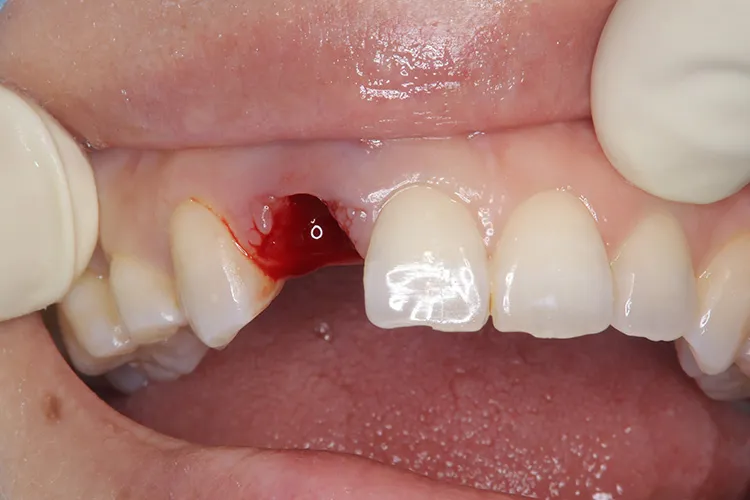

治療前

治療後

症例6/

前歯1本

- 治療期間

- 3ヶ月

- 費用

- 51万円(税込)

レントゲン画像

治療内容

怪我で歯が折れてしまったケースです。前歯なので抜歯即時埋入で対応しました。即時で仮歯まで入れ、見た目の回復を行いました。その後歯肉が治りインプラントが安定したタイミングで最終の被せ物を装着しオペから3ヶ月で治療完了しました。